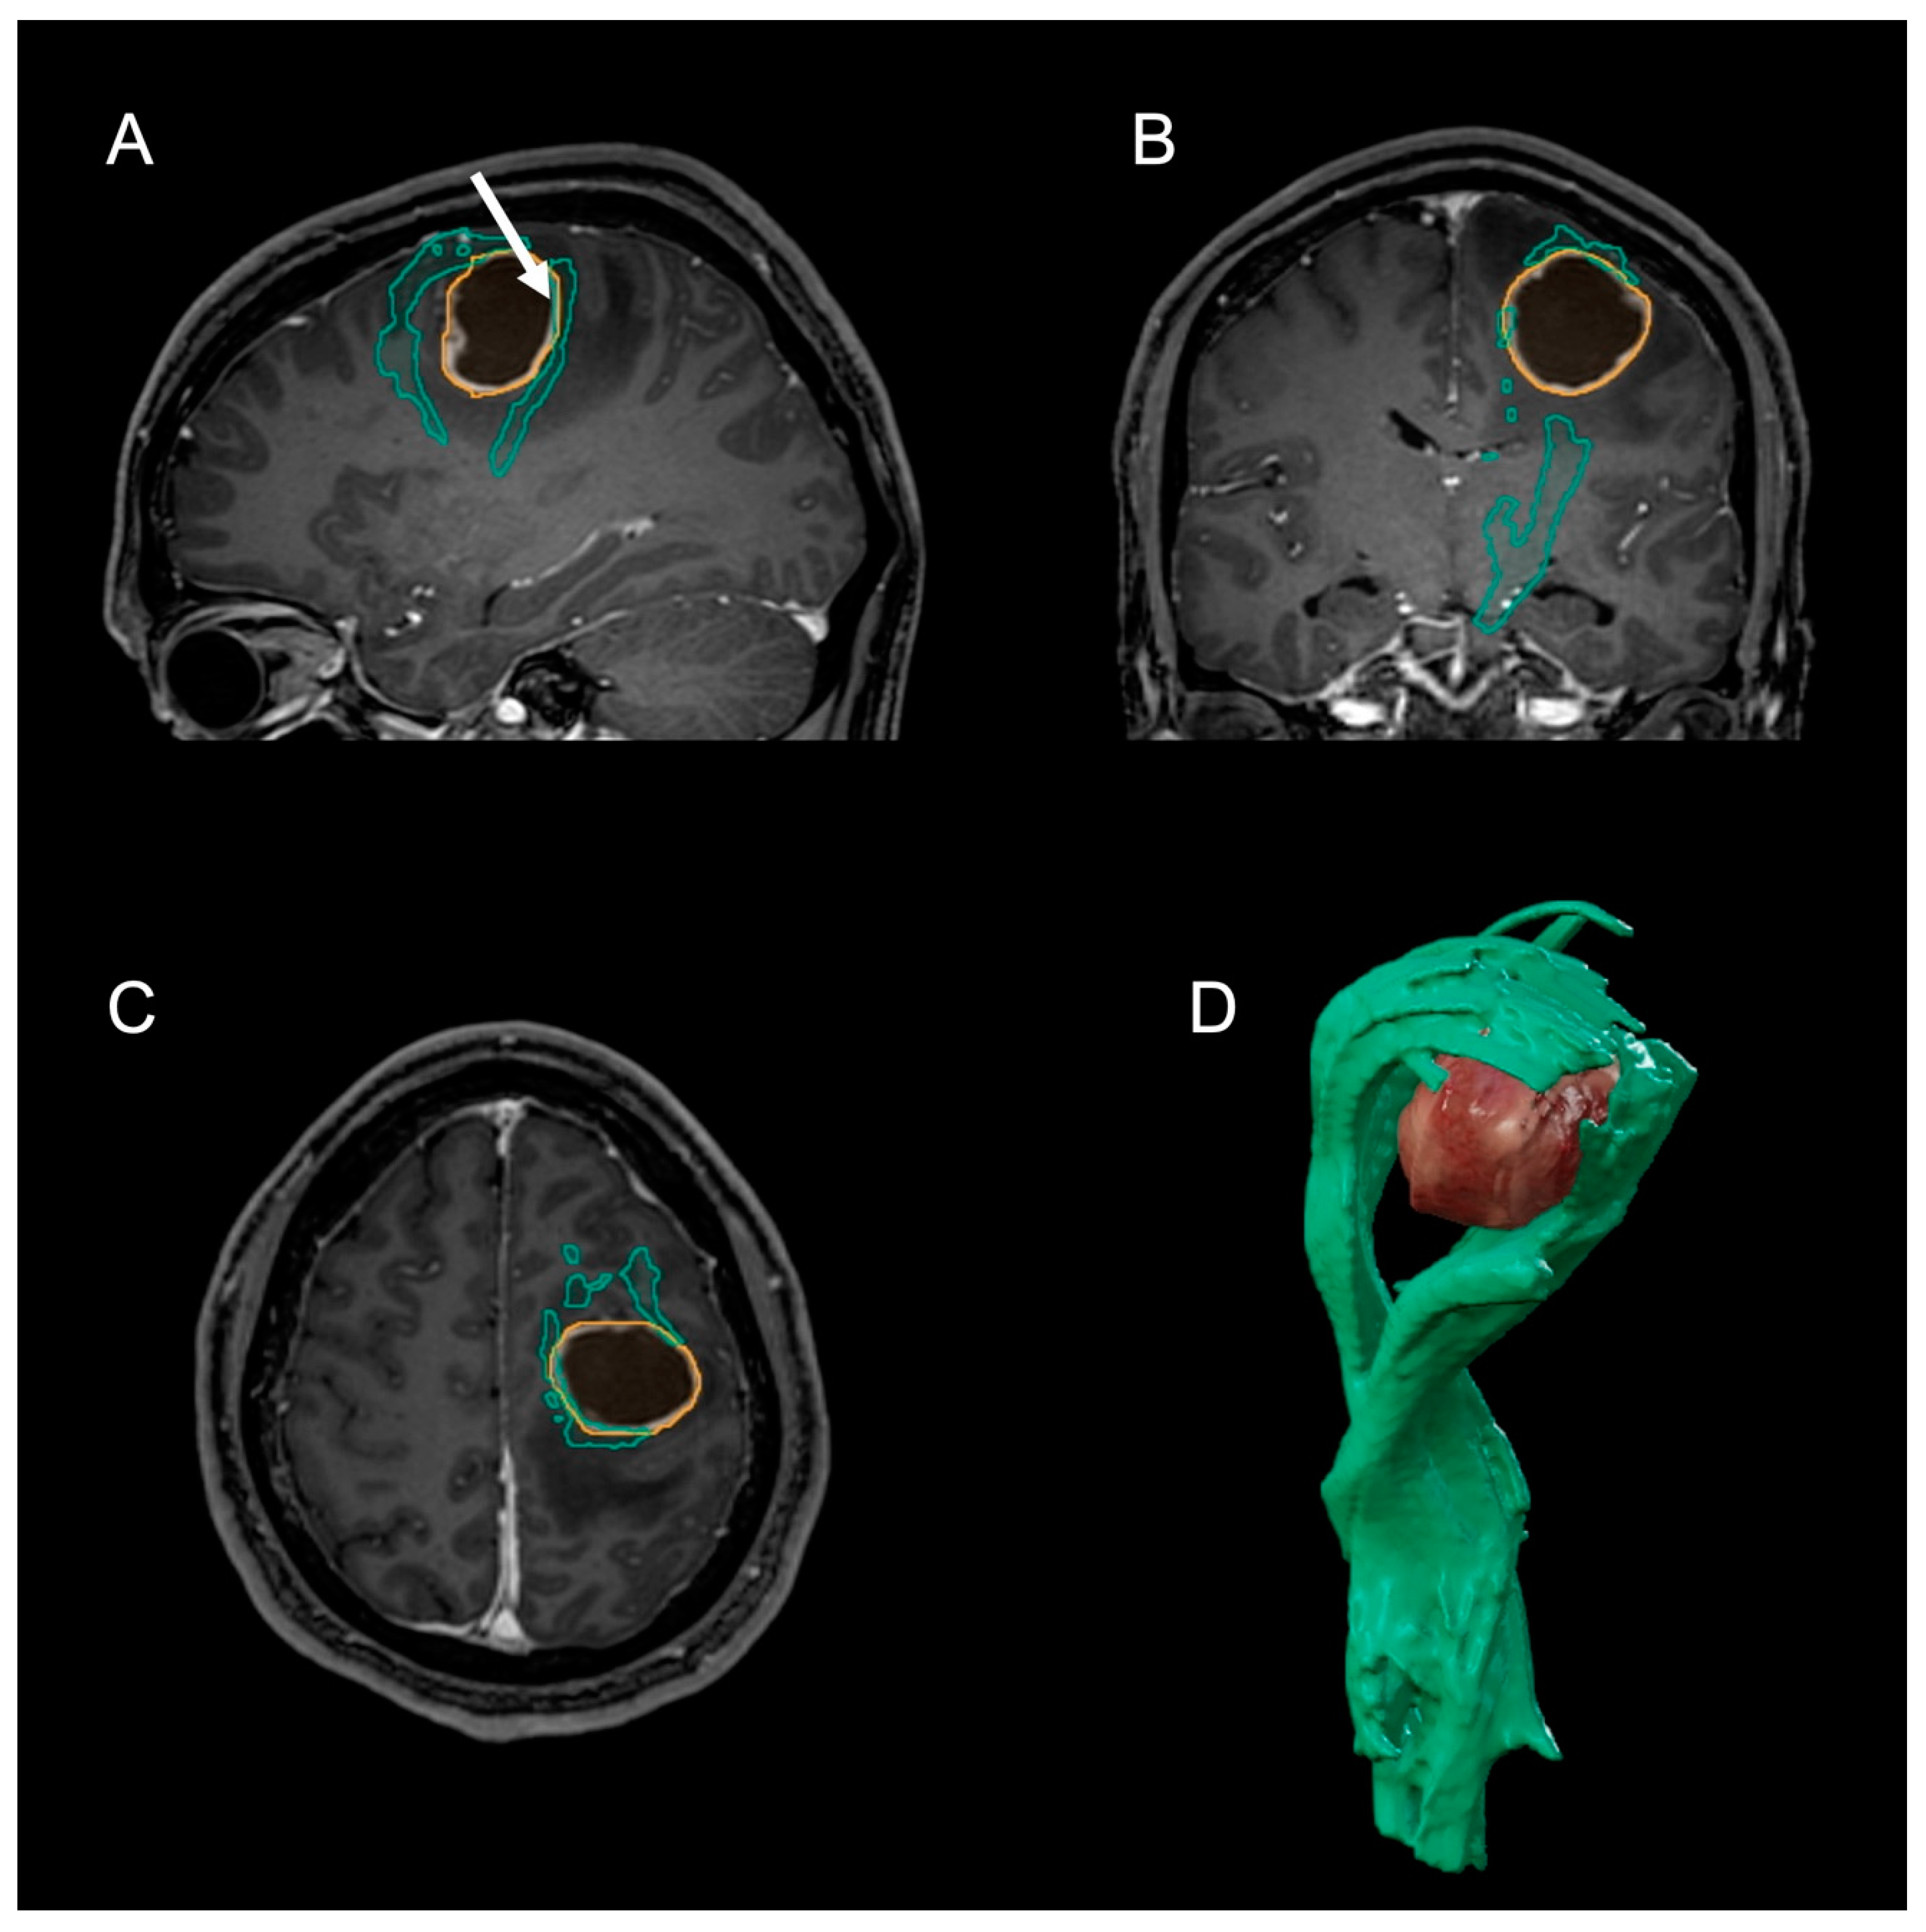

2. Case Presentation